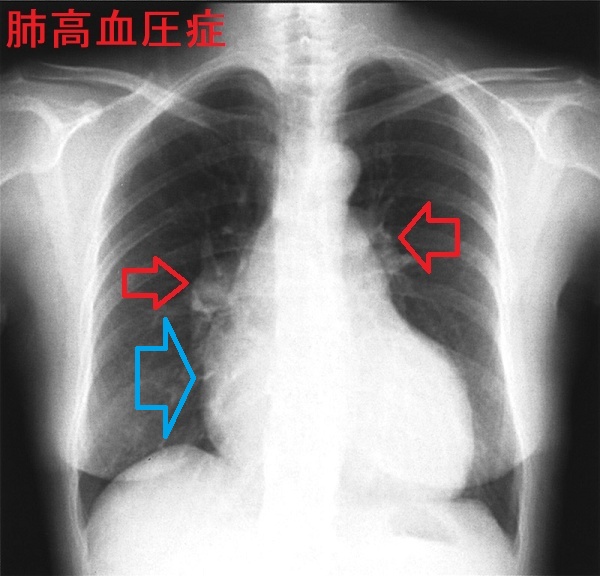

- 胸部エックス線検査;肺野に異常なし。左第2 弓突出(肺動脈主幹部の拡張)、右心房の拡大

甲状腺機能亢進症/バセドウ病では、元々、高拍出量性右心不全をおこしやすいが、右側胸水まで認めれば、肺高血圧症の合併を疑う必要があります。心エコー検査で右心負荷や肺動脈圧の評価が必須。

甲状腺機能亢進症 バセドウ病に肺高血圧症・右心不全を合併し、三尖弁閉鎖不全症(TR)も伴う。[Endocrinol Diabetes Metab Case Rep. 2018 May 16:2018:18-0012.]